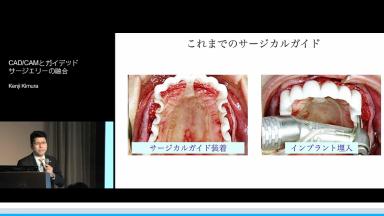

CAD/CAMとガイデッドサージェリーの融合

デジタルデータの活用は、プランニングから上部構造装着まで、計画的な治療の達成でき、患者様と歯科医師、そして歯科技工士のイメージを画像で共有し、物理的移動を省略し、アポイント回数の短縮につながる。さらにデータ上の設計を活用し、技工物製作期間を短縮でき、患者様への負担を減らすことのできる一つの方法である

- ストローマンガイデッドサージェリーの流れ、プランニングから上部構造製作まで一連の流れを理解できる